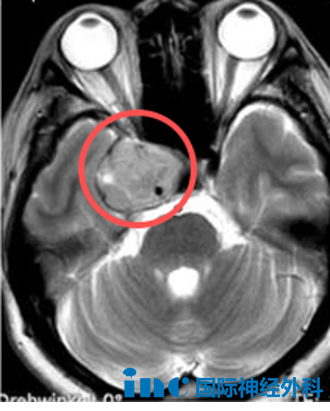

没想到,在做鼻窦CT时,无意之间扫到了脑部,发现脑子中间有肿瘤。我们立刻在当地医院做了核磁共振,确认肿瘤位于海绵窦区,大小约2.6*3.0*4.1cm。从那之后,我们全家开始了多方求医之路,先后去了北京、上海等地,可始终无法明确肿瘤的具体性质。